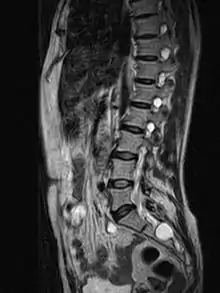

![]() | |

| MRI image showing a Tarlov cyst | |